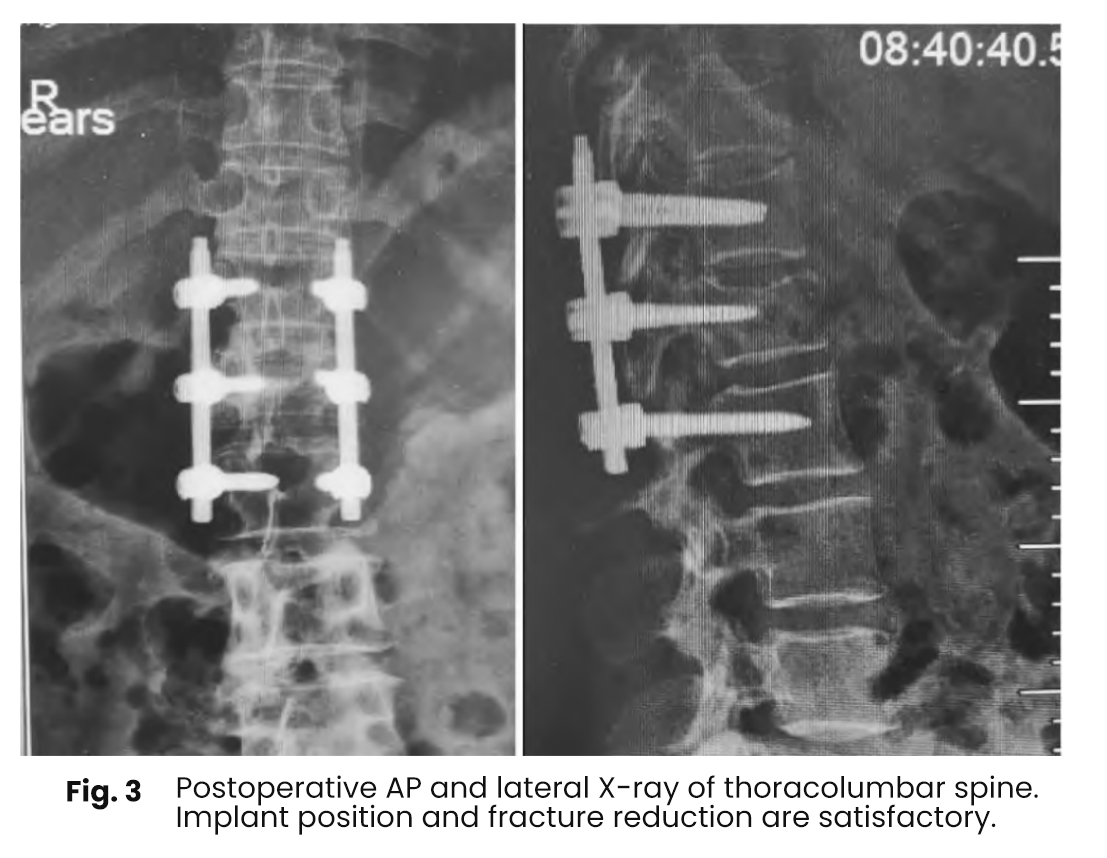

Postoperative imaging demonstrated significant improvement in kyphosis compared to preoperative status. All cases showed satisfactory fixation and reduction, with no evidence of vertebral clefts or cystic degeneration within the vertebral body.

Postoperative imaging follow up indicated a significant improvement in kyphosis correction compared to the preoperative state

In all cases involving bone grafting the pedicle screw rod fixation and reduction of the injured vertebrae were satisfactory